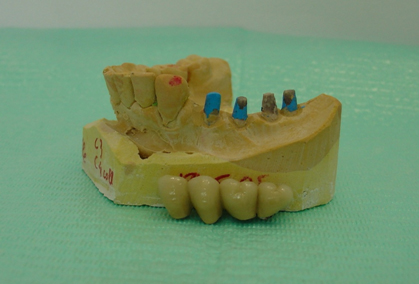

Se realiza un encerado diagnóstico en el laboratorio dental respetando los datos obtenidos durante el estudio del caso y en base al mismo se confecciona una férula quirúrgica convencional. Se colocan los cuatro implantes dentales mediante cirugía mínimamente invasiva sin colgajo. Al ser implantes dentales de una sola pieza, los muñones protéticos expuestos se fresan en boca con alta refrigeración para obtener un correcto paralelismo entre los mismos, y lograr así un ajuste sin tensiones de la prótesis fija implantosoportada.(F2)

Generalmente, respetando el encerado diagnóstico se confecciona una prótesis de resina acetálica, que se articula en boca, se pule y se cementa con Temp Bond (NR); y se realiza una Rx panorámica de control.(F3 y F4)